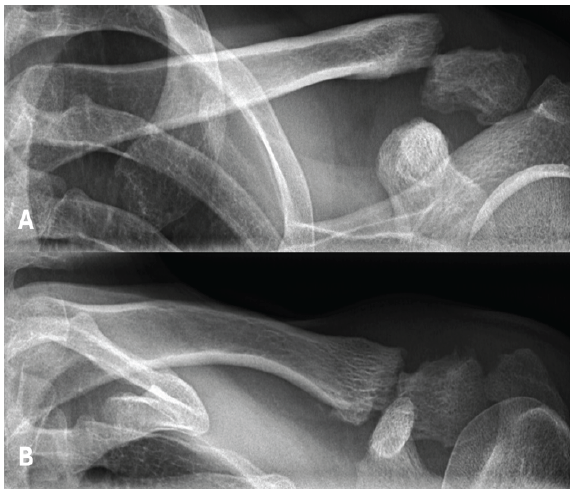

No perioperative complications were reported, and the wound healed appropriately. At the first follow-up X-ray (Fig. 2), taken 6 weeks postoperatively, a bone groove was observed in the clavicle at the level of the coracoclavicular loop augmentation. This groove became more pronounced and widened on the 3-month follow-up X-ray. However, fracture healing remained satisfactory, and the patient achieved full restoration of shoulder function without any reported pain or disabilities. Clinically, he demonstrated a highly satisfactory outcome with no limitations in daily activities.

Figure 2: X-rays at 3 months post-operative, showing good bone healing and the formation of a bone groove at the level of the coracoclavicular loop augmentation.

At 24 weeks postoperatively, the patient sustained a clavicle refracture at the site of the previous bone groove following a high-energy skiing accident (Figs. 3 and 4).

Figure 3: X-rays showing a refracture after a skiing accident, occurring 3.5 months after the initial all-suture osteosynthesis.